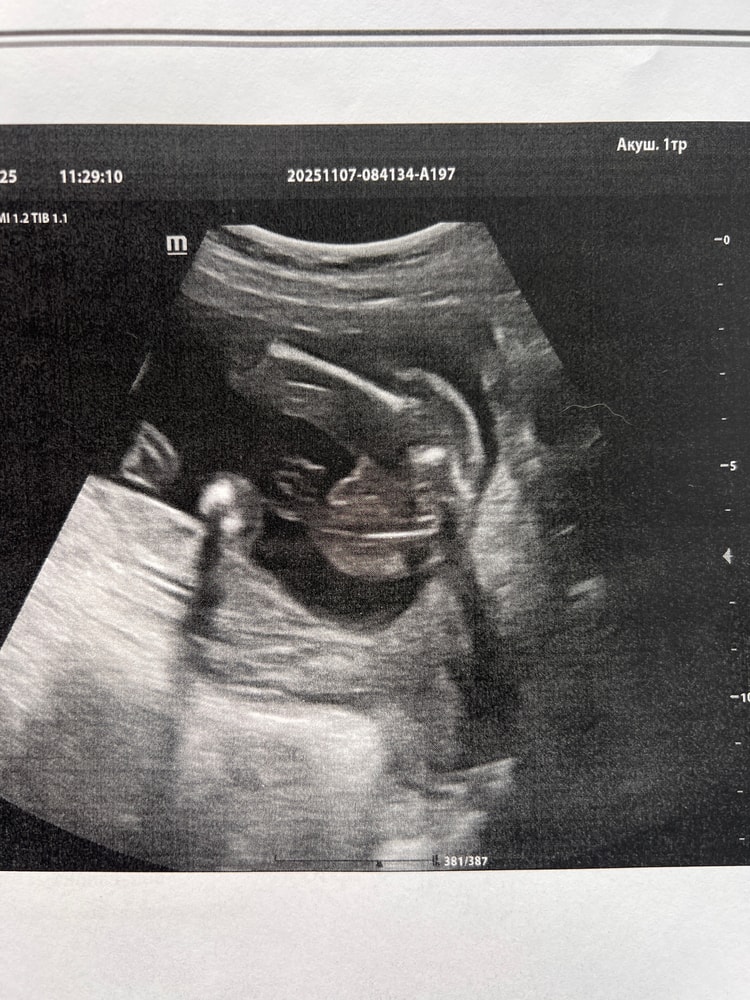

По первому фото я вообще понять ничего не могу . А вот тут оно самое ?😂 записалась еще на одно узи , через неделю. Уже не могу ждать ) или уже правда кровь сдать Изображение

09.11.2025

Маша, не эксперт, но мне кажется, что девочка. Может на 3д посмотреть?

Маша, по этому узи очень похоже что мальчик

Татьяна, у нас у мальчика. Прям пипка торчала, а тут как будто то ее нет

Libe, у нас тоже,помимо яичков пипка была,а на этом узи как будто просто яичники

10.11.2025

Евгения, как будь-то "пирожочек" плохо прорисованный

Маша, я вижу девочку

Евгения, 😌 где? Я тоже хочу ее увидеть 😅 вот это тогда что 🙈 Изображение

Маша, яичники это,а у мальчиков помимо этого ещё пипка торчит)

Евгения, я думала это и есть пипка 😂

Маша, да,только девчачья))ну я конечно не врач, но думаю так))

Маша, пипка прям пипка, палочка.